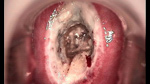

婦科leep錐切手術(shù) CIN2-3

• CIN 2-3 leep術(shù)后CIN 2-3 leep術(shù)后